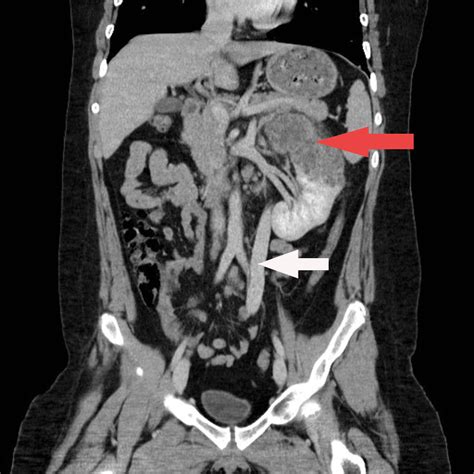

Ct of the abdomen and pelvis without contrast; • classically, the abdomen is divided into four quadrants defined by vertical and horizontal planes through the umbilicus. The anatomical planes are different lines used to divide the human body. Abdominal ct was performed to identify the exact location and the relationship to adjacent organs which revealed a huge retroperitoneal septate multilocular cystic lesion with the maximal diameter of 31 cm occupying almost the entire left half of the abdominal cavity ( figure 1, video 2, video 3). A coronal plane (also known as the frontal plane) is any vertical plane that divides the body into ventral and dorsal (belly and back) sections.

This is the template i use to interprate all of my ct of the abdomen and pelvis exams. Jeden tag werden tausende neue, hochwertige bilder hinzugefügt. Imaginary planes that intersect the body, creating slices of various organs and structures. Coronal plane topographic landmarks of the abdomen. Abdominal ct was performed to identify the exact location and the relationship to adjacent organs which revealed a huge retroperitoneal septate multilocular cystic lesion with the maximal diameter of 31 cm occupying almost the entire left half of the abdominal cavity ( figure 1, video 2, video 3).

Abdominal ct was performed to identify the exact location and the relationship to adjacent organs which revealed a huge retroperitoneal septate multilocular cystic lesion with the maximal diameter of 31 cm occupying almost the entire left half of the abdominal cavity ( figure 1, video 2, video 3). This is the template i use to interprate all of my ct of the abdomen and pelvis exams. Arteries of abdomen and pelvis, including inferior and superior mesenteric artery and branches of internal iliac artery. If given orally, you will be asked to drink a contrast liquid and then wait 90 minutes so the contrast can reach the abdomen. Normal abdominal ct in the transversal, coronal and sagittal directions. • classically, the abdomen is divided into four quadrants defined by vertical and horizontal planes through the umbilicus. This checklists serve as a guide to help you develop your. Dorsal indicates an area toward the back or spine, while ventral indicates the direction away from the spine, typically toward the ground. Patients often complain of an inability to maintain an upright posture; Filed under abdomen, anatomy, ct, pelvis. Ct of the abdomen and pelvis without contrast; A coronal plane (also known as the frontal plane) is any vertical plane that divides the body into ventral and dorsal (belly and back) sections. Abdomen (wl/ww 40/290 hu), bone (wl/ww 300/1500 hu).

Coronal volume rendered, ce ct of the superficial abdominal wall veins (from lawler lp, fishman ek: The indication for this examination is very important and is used to decide whether the examination is performed with oral. A plane is a 2d slice through 3d space, which can be thought of as a glass sheet. Coronal plane topographic landmarks of the abdomen. This poster shows one of a series of drawings which were created using adobe illustrator cs4 and adobe photoshop cs4. Filed under abdomen, anatomy, ct, pelvis. Collection ct scan of brain and multiple disease (left to right : Abdominal ct was performed to identify the exact location and the relationship to adjacent organs which revealed a huge retroperitoneal septate multilocular cystic lesion with the maximal diameter of 31 cm occupying almost the entire left half of the abdominal cavity ( figure 1, video 2, video 3).

Abdominal ct was performed to identify the exact location and the relationship to adjacent organs which revealed a huge retroperitoneal septate multilocular cystic lesion with the maximal diameter of 31 cm occupying almost the entire left half of the abdominal cavity ( figure 1, video 2, video 3). The following 150 files are in this category, out of 150 total. A plane is a 2d slice through 3d space, which can be thought of as a glass sheet. The indication for this examination is very important and is used to decide whether the examination is performed with oral. The labeled structures are (excluding the correct side) This page provides a photo gallery that presents the anatomy of the abdomen by means of ct (axial, coronal, and sagittal reconstructions). The same normal abdominopelvic ct without labels for reference. The following are three ct scans that the abdomen performed both with and without intravenous contrast. Computed tomography of the abdomen and pelvis, performed as a contrast ct, here presented in the sagittal, en:coronal planecoronal and axial plane, with 3 mm slice thickness. • classically, the abdomen is divided into four quadrants defined by vertical and horizontal planes through the umbilicus. If given orally, you will be asked to drink a contrast liquid and then wait 90 minutes so the contrast can reach the abdomen. This is ct abdomen/pelvis (coronal) by thame on vimeo, the home for high quality videos and the people who love them. Coronal volume rendered, ce ct of the superficial abdominal wall veins (from lawler lp, fishman ek: